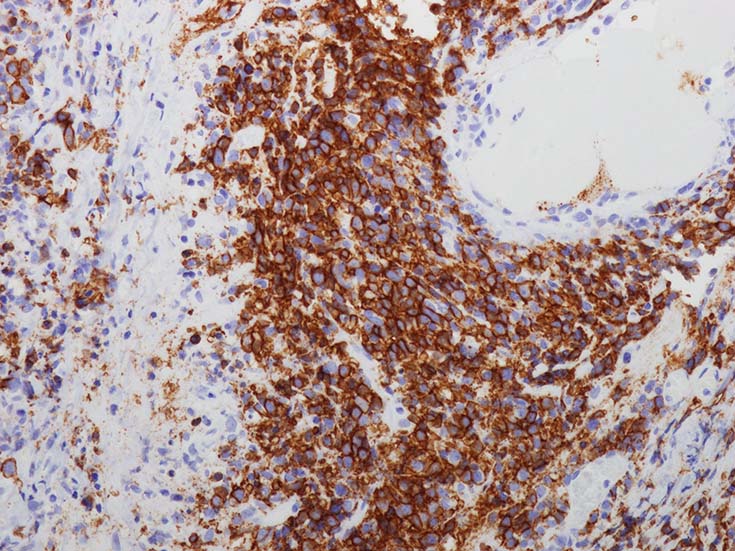

免疫染色

血管中心性浸潤. 障害された血管内に血栓が形成されている.CD20陽性細胞がシート状密に浸潤, CD3陽性T細胞が多く混在している. EBER-ISH陽性 EBV感染細胞が多数認められ, >50 hpf, 定義より Grade3となる. 陽性細胞のサイズは大小さまざまであることに注意.